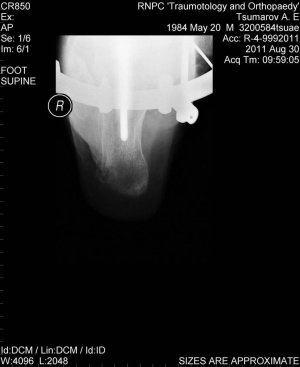

Возник вопрос об упражнениях для реабилитации после перелома голени и пятки (реабилитолог поликлиники сейчас в отпуске). Перелом произошел 3 месяца назад, наложение аппарата Илизарова осуществлено на неделю позже.

На данный момент могу поднимать стопу на 1 см максимум со слабым усилием, также создавать небольшое на опускание стопы. Пальцы но могу опускать (вжимать) нормально, но принципиально не могу поднимать (разжимать). Опухлость верхней части стопы держится все 3 месяца.